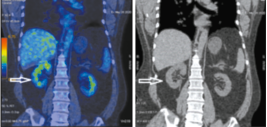

На совмещенных ПЭТ/КТ- и КТ-проекциях с использованием 18-фтордезоксиглюкозы в правом надпочечнике определяется объемное образование размером 79×54×41 мм с ровным нечетким контуром, неоднородной структуры за счет наличия гиподенсных аметаболических участков некроза с повышенной метаболической активностью фтордезоксиглюкозы SUVmax 7.25. Верхнелатеральным контуром образование прилежит к нижней поверхности печени (граница четко не дифференцируется), нижним контуром – к верхнему полюсу почки (жировая прослойка прослеживается), а медиально – к ножке диафрагмы (рис. 1, 2).

Рис. 1. Пациент У., 52 года. Корональная ПЭТ/КТ- (а) и КТ-проекция (б). В правом надпочечнике опухоль размером 79х54х41 мм (стрелка), с гиперфиксацией радиофармпрепарата SUVmax 7.25.

Fig. 1. A 52-year-old patient U. positron emission and computed tomography (PET/CT) (a) and CT images in coronal projection (b). A 79×54×41 mm mass (arrow) in the right adrenal gland, associated with elevated fluorodeoxyglucose metabolic activity SUVmax 7.25.

Рис. 2. Пациент У., 52 года. Аксиальная ПЭТ/КТ- (а) и КТ-проекция (б). В правом надпочечнике опухоль размером 79х54х41 мм (стрелка), SUVmax 7.25.

Fig. 2. A 52-year-old patient U. PET/CT (a) and CT images in axial projection (b). A 79×54×41 mm mass (arrow) in the right adrenal gland, SUVmax 7.25.